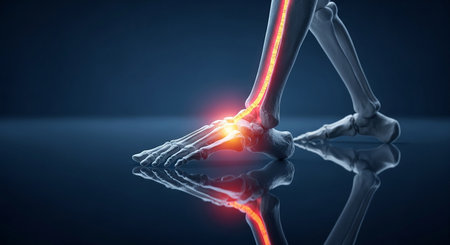

3d rendered illustration of a painful ankle joint

Bone ankle joints of humans with inflammation

Detailed depiction of an ankle joint injury highlighting pain points, human anatomy, and health implications in a clinical style illustration

3d rendered illustration of a painful ankle joint

3D render of a medical image of close up of ankle bone in foot highlighted